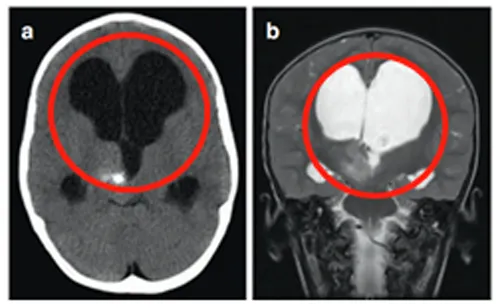

3岁患儿马修被发现丘脑病变,但因手术风险较高采取保守观察长达10年。随着患儿成长,病变并未停止发展。初始症状仅为呕吐,逐渐进展为上肢震颤,最终发展为急性偏瘫。病变在十年间持续增大数倍,并出现多个新生囊肿。

马修最初因呕吐症状及头围较大就诊,检查发现右侧丘脑存在伴钙化表现的病变,同时合并第三脑室梗阻引发脑积水,这些因素共同导致影像学显示的异常扩大。

由于症状轻微而手术风险过高,术后可能较现状更差,医生评估认为不具备手术指征。然而肿瘤持续生长并形成多个小囊肿。同侧内囊(负责肢体运动功能)向前外侧移位,导致患儿从左上肢震颤进展为急性偏瘫。

马修首先接受神经导航和超声引导下活检,病理证实为WHO I级毛细胞星形细胞瘤。为治疗多发性囊肿,就诊于INC鲁特卡教授后植入Ommaya囊,并在超声引导下将导管置入肿瘤囊性成分。MRI复查显示囊性占位解除,脑室形态逐渐恢复正常。

4个月后偏瘫症状未改善,鲁特卡教授又为其行经胼胝体半球间入路肿瘤切除术,成功切除肿瘤。术后患儿偏瘫症状改善,生长发育和智力发育均恢复正常水平。